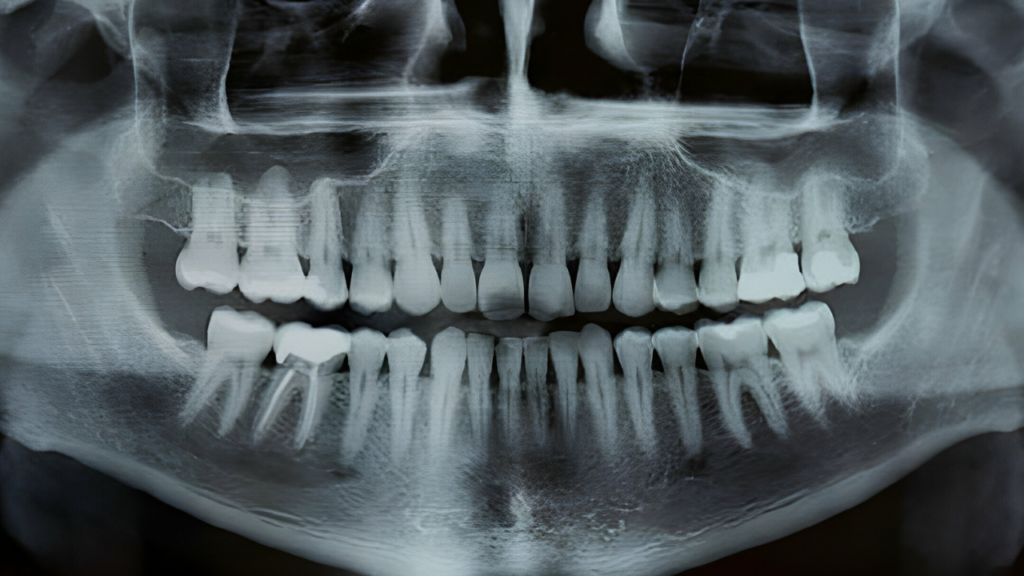

O raio X panorâmico odontológico, que também pode ser chamado de ortopantomografia, é um exame de diagnóstico geralmente solicitado no início de tratamentos dentários, que emite imagens da mandíbula e do maxilar no mesmo quadro de forma panorâmica.

Ou seja, em uma mesma imagem é possível ver todas as estruturas do maxilar e mandíbula, sendo esse exame extremamente útil e considerado pelos cirurgiões-dentistas uma das melhores formas para realizar análises de diversas ocorrências da odontologia, como identificação de enfermidades nos dentes e ossos faciais.